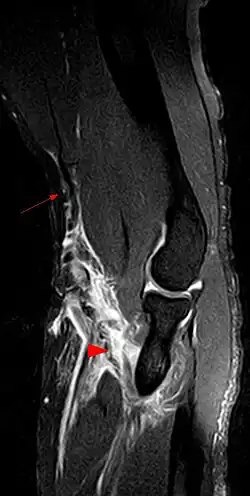

Untersuchungsmethoden

- MRT